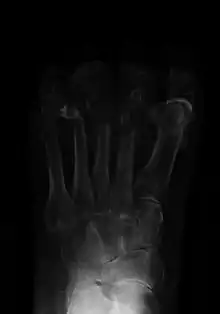

Osteomyelitis of the 1st toe

Extensive osteomyelitis of the forefoot